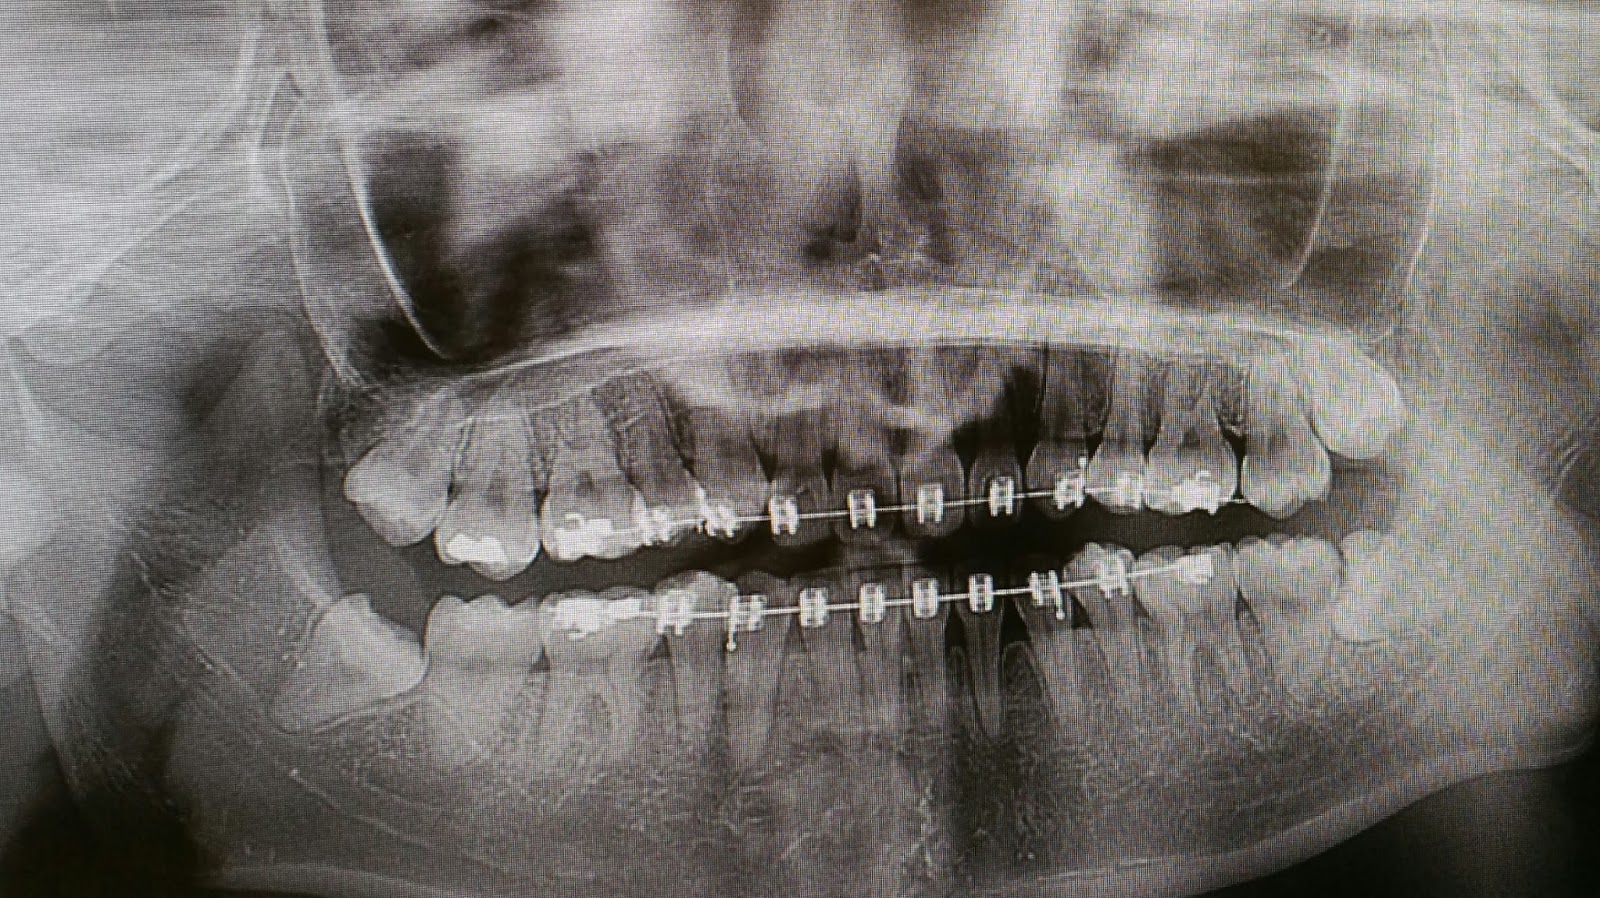

I was also very lucky to have met Dr Noah because he was very gentle and patient, and nice to talk to. Apparently he did my boyfriend's wisdom teeth extraction too (talk about coincidence). Okay so I needed a lot of calming down because my BP and HR was high and i had just taken 2 puffs of ventolin (the nurse was worried I might get an asthma attack during the procedure so yeah just a preventive measure) and he tried to be as gentle and offered a lot of care and concern. He joked with me and had a small conversations with me while his nurses get me settled. He was very surprised that I wasn't offered GA (i guess partly because i wanted them removed today) and was even more surprised to know that I settled with LA when i wanted to remove all 4 of them today. I am also a very impatient person who wants to get things done asap so yeah, why not? I really recommend people going to the hospital even if it meant that you have to do a walk-in (even better if you can wait and have an appt scheduled for you) because my sister recently went for hers at the clinic and ONE TOOTH cost $1000++ and my mum was told that the upper one which is scheduled to be removed in about 1 or 2 more days time cannot be deducted from medisave. That's bullshit really. I had all 4 extracted at $1200+ and it is fully deductible via medisave (thank god for medisave). I only had to pay a cash of $70 for both X-ray and consultation. The procedure included all the drugs and consumables. I think the procedure was quite fast but it was a little scary because I was shivering throughout especially when he drilled my teeth. The upper one was quite nicely extracted. I'd love to show you my teeth but it will probably gross you guys out but I will keep it at the bottom of this post along with my x-ray.